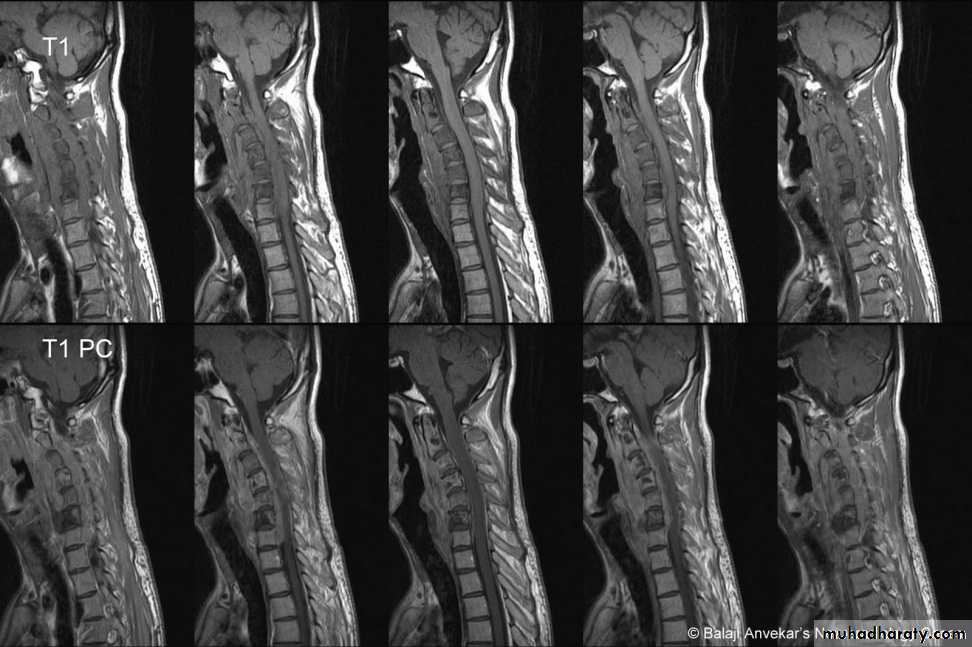

DIAGNOSISX RAY

Anterio posterior X ray radiograph.lateral radiographs with the head in flexion and extension may revealinstability that is not shown in the routine lateral film.

through the open mouth.Computed tomography (CT)

and magnetic resonance imaging (MRI).

The standard method of treatment may, therefore, be said to be conservative.BURST FRACTURE OF A VERTEBRAL BODY

the compression force thus acts vertically in the line of the vertebral bodies.

The intervertebral disc is forced

In the affected vertebral body, causing a comminuted bursting fracture in which fragments are driven outwards in all directions.